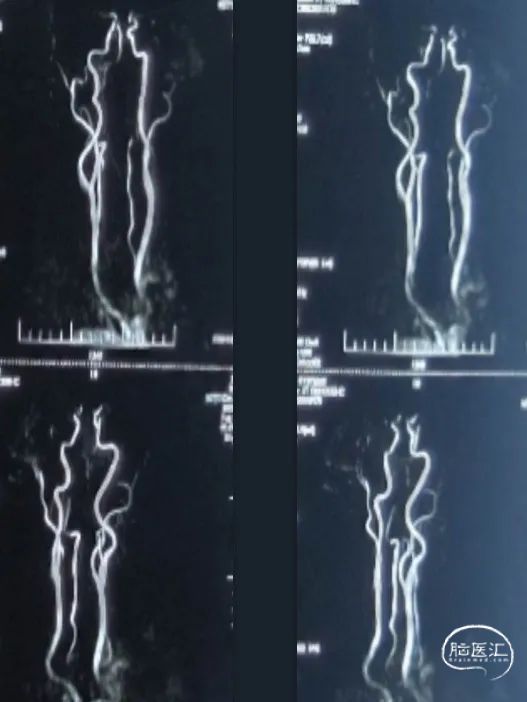

外院头MRI+颅颈MRA(2023.02.07):双侧基底节区腔隙性脑梗死,双侧椎动脉颅内段显示不清,颈动脉及基底动脉未见明显狭窄。

外院DSA(2023.02.09):左侧椎动脉V4段重度狭窄,右侧椎动脉V3段远端闭塞。前循环未见明显异常。